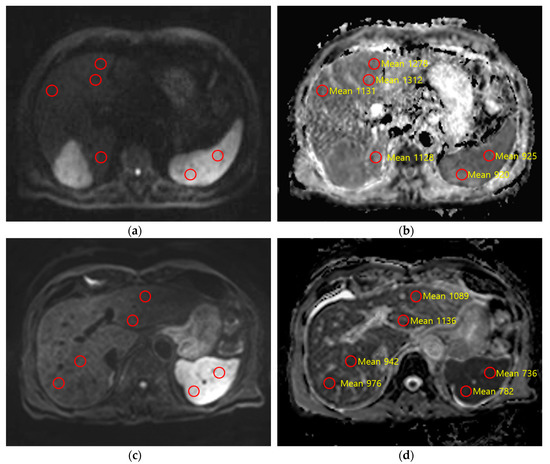

2.3. Quantitative Image Analysis